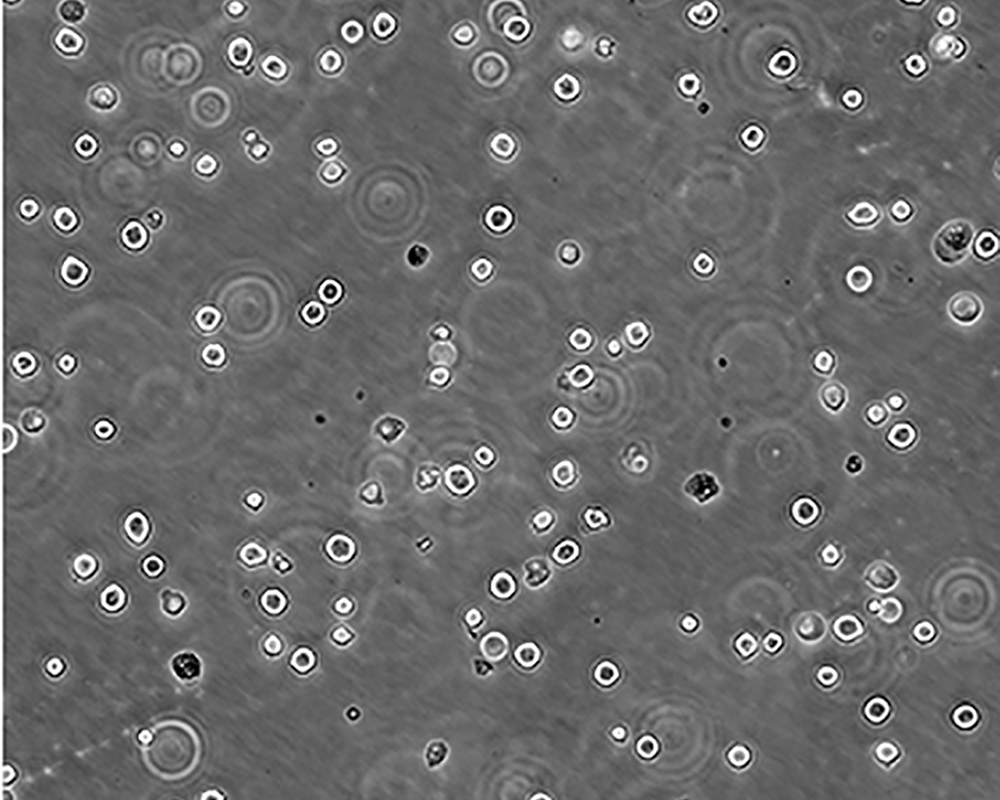

K-562 [K562]細胞

產品名稱 K-562 [K562]細胞

中文名稱 人慢性髓原白血病細胞

組織來源 慢性髓細胞白血病;女性

生長特性 suspension

形態特征 lymphoblast

細胞描述 The cell population has been characterized as highly undifferentiated and of the granulocytic series. Studies conducted by Anderson, et al. , on the surface membrane properties led to the conclusion that the K-562 was a human erythroleukemia line. K-562 blasts are multipotential, hematopoietic malignant cells that spontaneously differentiate into recognizable progenitors of the erythrocytic, granulocytic and monocytic series. The effect of inducers on sublines derived from the original K-562 cell line have been reviewed by Koeffler and Golde. Karyological studies on various K- 562 sublines have been classified into three groups(A,B,C) by Dimery, et al. The strain obtained by the ATCC most closely resembles the B population. Occurrence of the Philadelphia chromosome, however, was of much lower frequency; none detected in 15 metaphases examined. The line is EBNA negative.